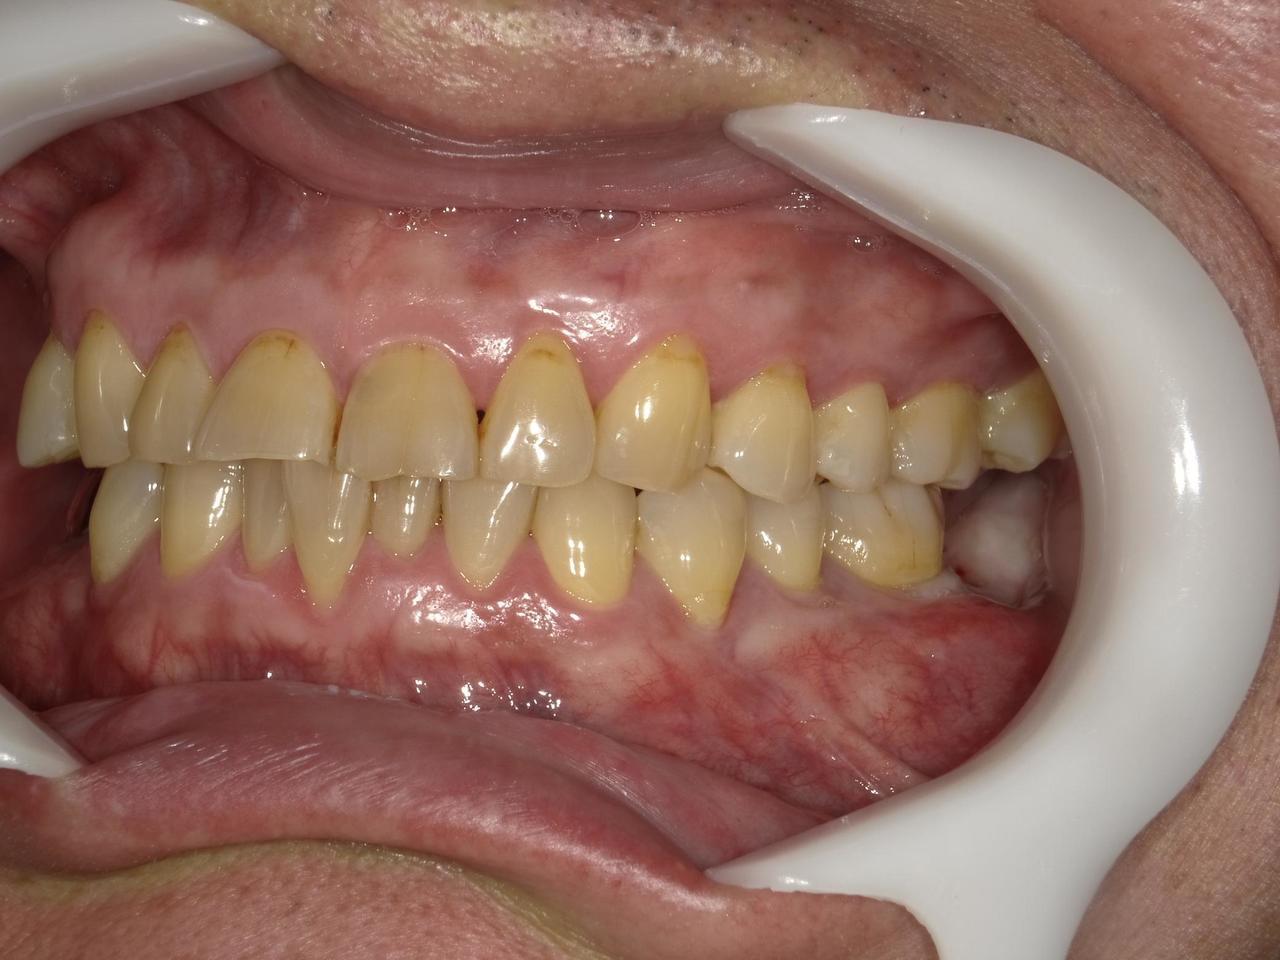

5.左上4番のインプラント抜歯即時埋入、左上6番の上顎既存骨1から2mmのグラフトレスサイナスリフト、左下56の大幅な骨欠損により、下顎神経の損傷を回避するために、ショートインプラントを使用し、左下56にインプラントを埋入し、最終補綴物は、左上456の3ユニットのジルコニアブリッジし、左下56は、ジルコニアの連結冠を装着したケース

M・I 様 女性 70代

症状としては、左下56は、歯周病で欠損したと考えられるが、かなりの骨欠損をともなっていた。左上456に関しては、動揺が大きく、炎症が起き、排膿、および、歯性上顎洞炎を起こしていた。

治療法としては、動揺がひどくなってきて、炎症の症状もあったため、左上56の抜歯を希望。インプラント治療をその後、希望したため、左上4に関しては抜歯即時埋入。左上6に関しては、既存骨1から2mmでインプラント治療が厳しい状態であったが、グラフトレスサイナスリフトを行い、治療期間5か月はかかるということを説明して、インプラント埋入をおこないました。その後、2か月半後、大幅に骨が欠損している下顎56に対して、ショートインプラントを使用して、下顎神経の損傷を避けて、インプラント埋入を終えています。その後2か月後に光学印象で印象を行い、上顎刺億456歯、3ユニットのジルコニアブリッジを装着。下顎左側56に関しては、骨欠損が大きいため、歯冠長がだいぶ長くなるため、ジルコニアの連結冠を装着して治療を終えた。

治療結果は、上顎6に関しては、既存骨が少なく、厳しい治療ではありましたが、5か月で治療を終え、患者様の負担を最小限に抑えるができたと考えます。(従来のサイナスリフトでは、このようなケースでは1年以上、1年程度の治療期間がかかるか、治療が不可能と言われるケースだと考えます。)また、下顎は骨欠損が大きく、下歯槽管のリスクが起きることが考えられますが、ショートインプラントを使用することで安全に治療を行うことができました。

治療の期間・回数:治療期間5か月(上顎456 3ピースブリッジの治療は5か月(上顎既存骨が2mm程度しかなく、骨結合に時間がかかるケースであったために、5か月の治療期間が必要であった。)(左下56に関しては2か月半で治療を終えています。)治療回数は、13回。

治療の価格:1,474,000円(税込)